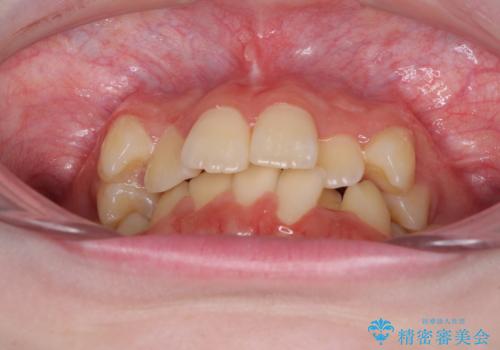

- 上下前歯のデコボコを気にして来院された患者様です。

前歯の叢生は強かったのですが、口元が引っ込んでいる印象であったため、非抜歯にて矯正治療を行うこととしました。